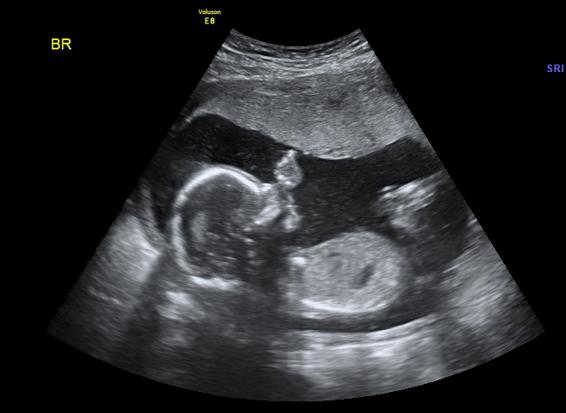

Semana 17 para el bebé

El bebé en las semana 17 mide unos 12 cm (como un aguacate) y pesa 100g. Obtiene mucho nutrientes a través de la placenta, pero apenas tiene grasa. Por eso a medida que crece, su rostro presenta un aspecto más alargado.

Por otra parte, ya tiene un poco de pelo en la cabeza y le están saliendo las cejas e incluso las pestañas.

Utiliza sus rasgos, formados con todo detalle, para ensayar distintas expresiones. Su caja torácica también está activa, pues practica movimientos respiratorios, aunque lo que aspira es líquido amniótico, no aire.

En resumen, esta es una etapa muy activa. No tardarás mucho en notas sus movimientos.